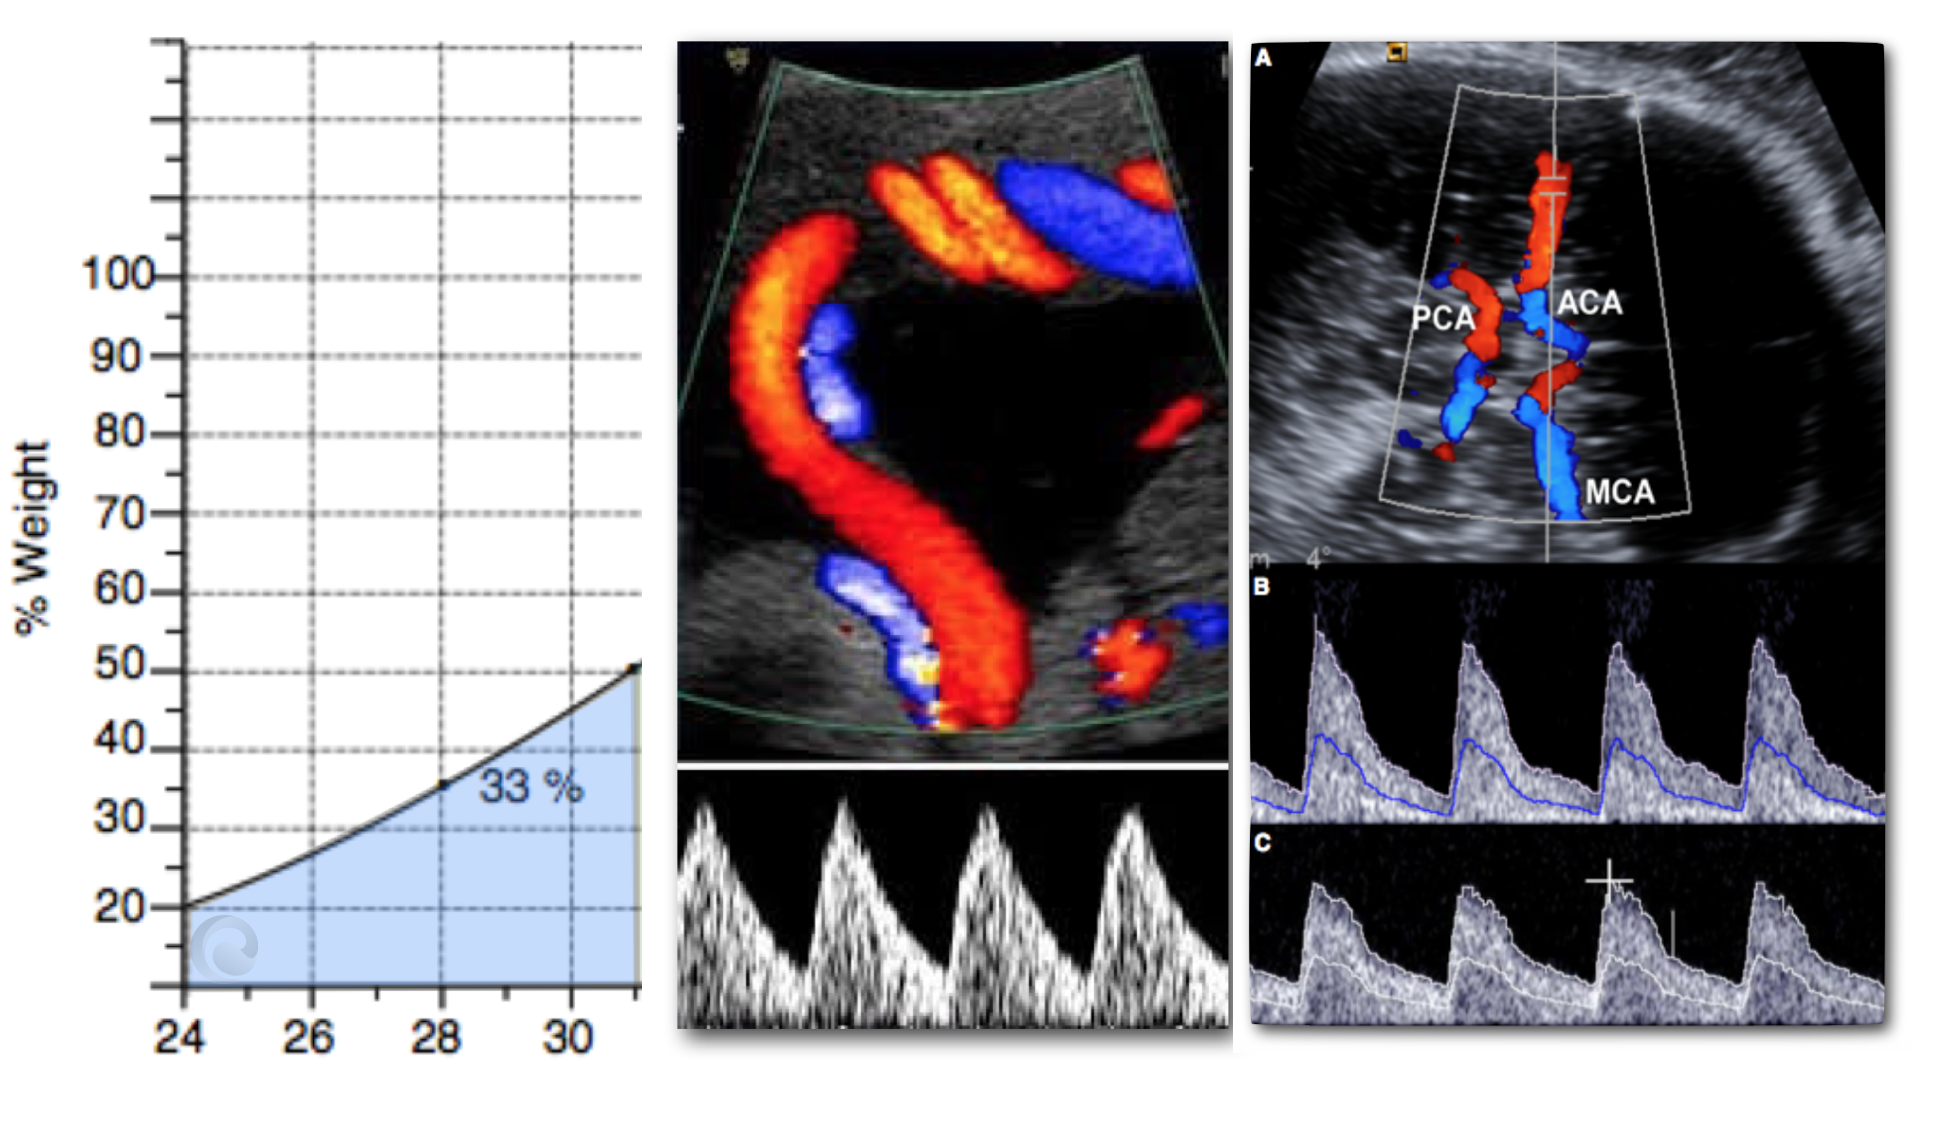

GRÁFICOS:

1. Doppler umbilical

2. Tablas de crecimiento